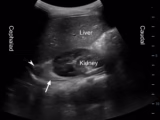

Giant Pyonephrosis Diagnosed Using POCUS in a Resource-Limited Setting

Roody Menager; Rebecca St Louis; Anst Gelin; Flawendjee Djaweelentz Jacques - This case discusses a 36-year-old man presented to the ED with dyspnea, fever, abdominal pain, and abdominal distention in the area where an intra-abdominal tumor was reported. After ultrasound-guided aspiration, pyonephrosis was diagnosed. In the absence of other capable specialists, the emergency physician performed [...]